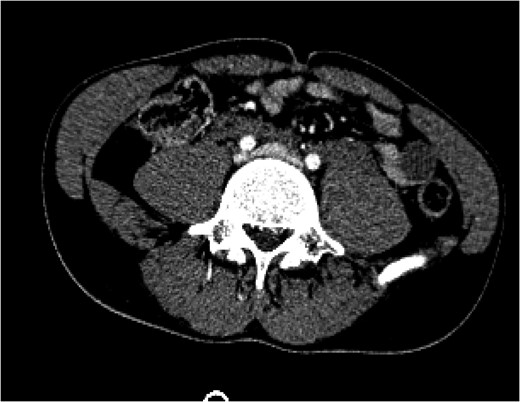

Figure 3:

A CT angiogram of the chest with and without contrast on Day 16 showed resolution of the pseudoaneurysm in the proximal left common iliac vein with clear flow at the IVC bifurcation.